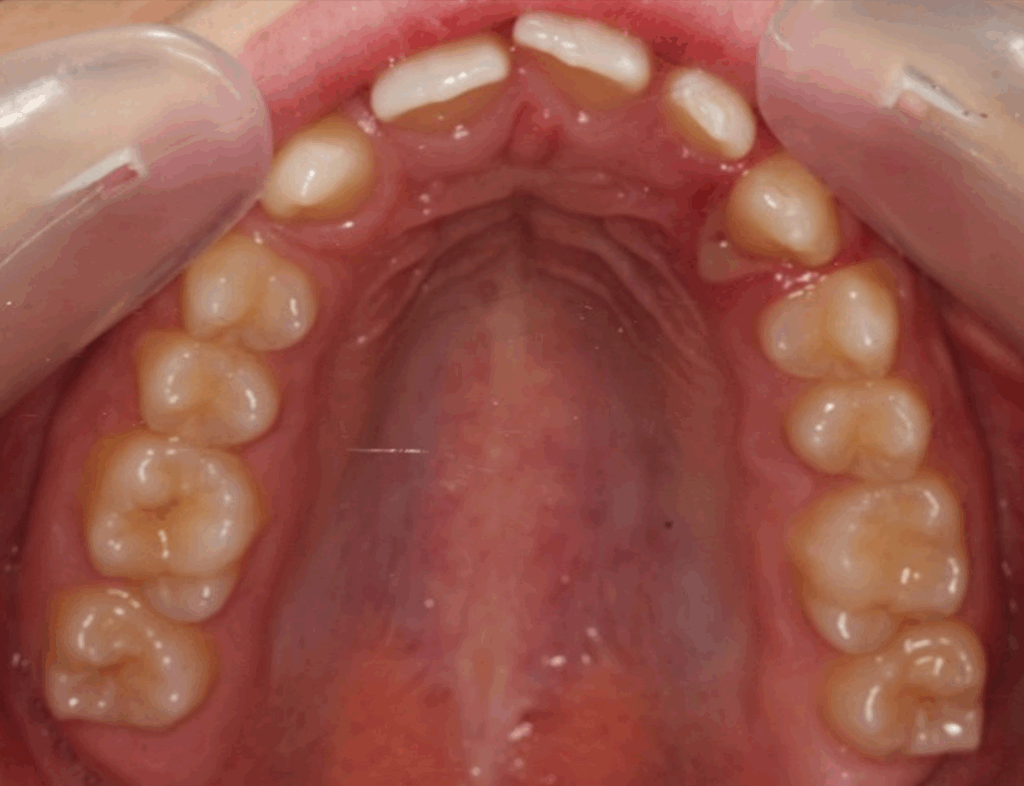

Skeletal Class II due to mandibular retrognathia, proclination of maxillary incisors, narrow arch creating a V-shaped arch, agenesis of 12, 31, 41, hyperdivergent facial pattern, moderate deep bite (2 mm), increased overjet (9 mm), asymmetric canine and molar Class II due to mandibular deviation to the left, maxillary midline deviation related to agenesis of 12, distal rotation of 35 and 45, and pronounced lower curve of Spee.

Transverse expansion

Space opening for 12 by distalizing 13

Maxillary midline correction